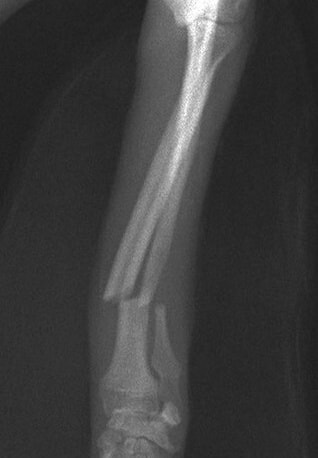

橈尺骨骨折 : 症例1 | 症例2 | 症例3 | 症例4 | 症例5 | 症例6 | 症例7

: 症例8 | 症例9 | 症例10 | 症例11 | 症例12 | 症例13 | 症例14

: 症例15 | 症例16 | 症例17 | 症例18 | 症例19 | 症例20 | 症例21